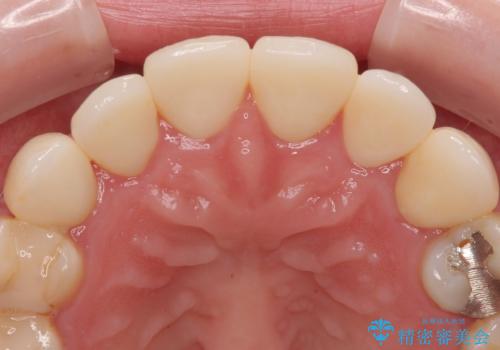

被せものが出来上がってから数回形や色の修正がありましたが機能的にも見た目も大変満足していただきました。

また個歯トレーによる型どりは頬粘膜や舌により型どりが困難な時には大変有効です。

今後は奥歯の治療に取り掛かっていく予定です。